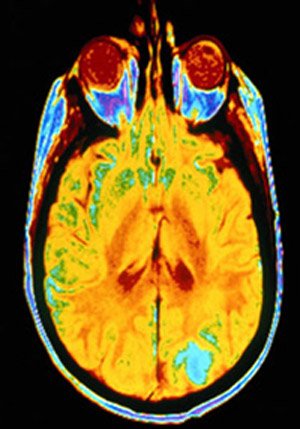

ويستخدم الرنين المغناطيسي مجالا مغناطيسيا لقياس كمية تدفق الدم في المخ. ويمكن ان يظهر اي مناطق في المخ هي الاكثر نشاطا من الاخرى لكن ذلك يتطلب تفسيرا حذرا ودقيقا. وشملت تجربة فولك 20 متطوعا من الرجال والنساء.

وفي تجربة دارت حول الكريمات الواقية من الشمس توقع نصف المتطوعين بشكل صحيح سلوكياتهم في هذا المجال. وحلل الباحثون صور الرنين المغناطيسي في مسعى لرصد منطقة نشاط في العقل تعطي نتائج أفضل من 50 في المئة. وقدمت أفضل المعلومات منطقة معينة في العقل موجودة في اللحاء الامامي الاوسط.

وقال ليبرمان "من هذه المنطقة من العقل تمكننا من التكهن بشكل صحيح بنسبة ثلاثة ارباع (75 في المئة) ما اذا كانوا سيزيدون استخدامهم للكريمات الواقية من الشمس كما يقولون." وأضاف "هذه المنطقة لها علاقة بمعرفة الذات ويبدو انها تنتقد طريقة تفكيرك في نفسك وما تفضله."